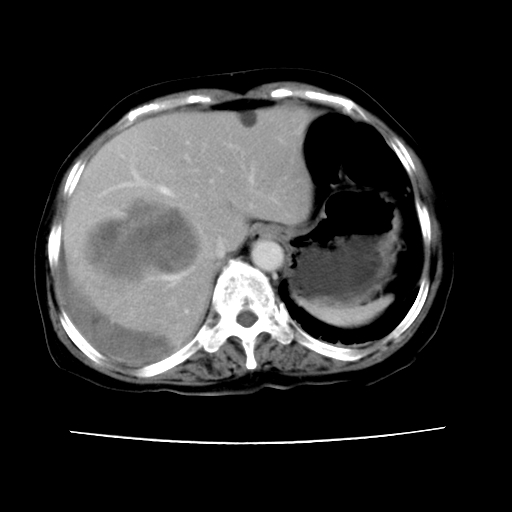

2008-11-10ct平扫(其间去中山医院诊治未行特殊治疗)

2008-11-10ct平扫见并肝内、血膜下血肿基本吸收,肝内低密度灶缩小。此时再做增强ct应有显着意义。对患者/医者都好!

从平扫+增强及治疗后复查片,病变明显缩小,不考虑肝癌出血可能,还是考虑为良性病变可能性大;单纯血肿并包膜下积液吧,病变强化没法解释,肝血管破裂出血吧,增强不符合典型血管瘤的表现,良性肿瘤破裂出血吧,复查片看来好像也不太支持(没做强化也不太好说)。本人还是考虑单纯肝内血肿并包膜下积液,强化是不是血管有外渗。

患者自6月至11月,如果是肝癌,没有经过特殊治疗,想必应该会有所进展吧,而不是ct所见,反而似有病灶减小的趋势。建议增强。

同意肝内肿块破裂致腹部疼痛,但不考虑肿瘤及血管瘤,增强不是血管瘤的特点,肿瘤半年时间内未经特殊治疗竟然快消失?考虑炎性改变或脓肿或寄生虫

病变破裂出血应首先考虑,病变性质即可能是恶性也可能是良性,楼主说患者到上级医院检查未见癌细胞,以良性可能性大,首先考虑腺瘤破裂出血可能。

追问病史,患者有过度用力病史,当时立即感腹痛;所以还考虑肝破裂可能性大。